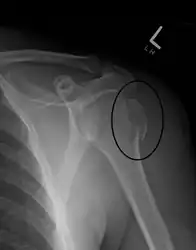

Proximal humerus fracture -

Fracture dislocation of the right shoulder